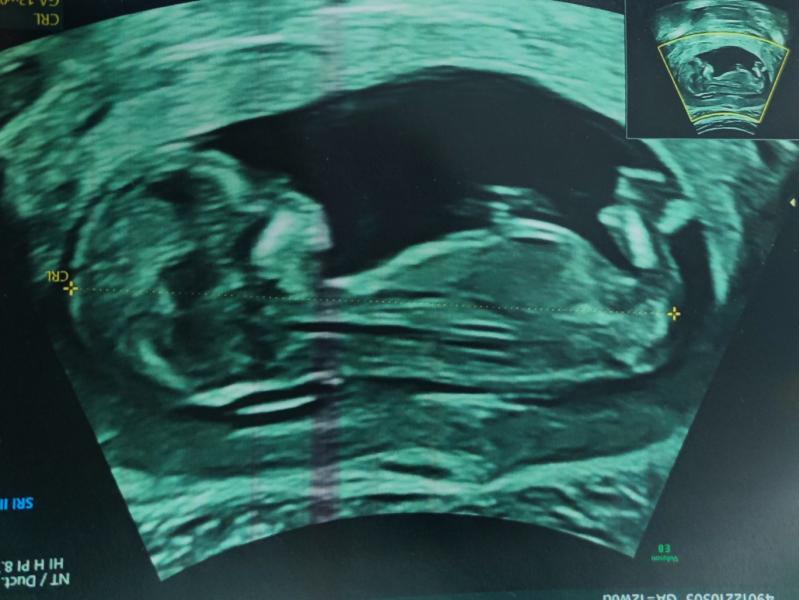

Фотографии просто 🔥🤣🤣🤣

А вторая фотография просто 💣🔥🔥🤭